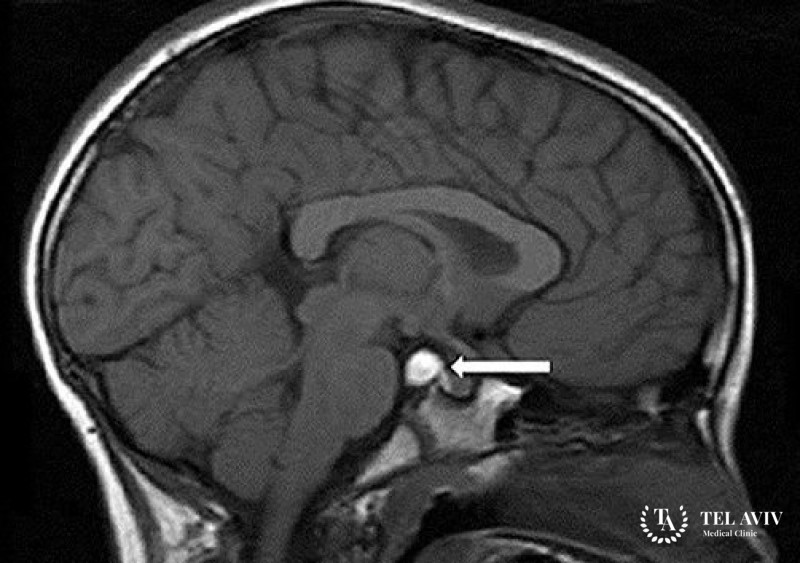

Шишковидные кисты возникает в железах головного мозга с аналогичным названием. Они представляют собой кистозные, очерченные образования. Локализация – пинеальное тело, эпифиз. Располагаются во внутренней части. Внутри кист находится жидкость. Этот тип образований прогрессирует медленно, увеличение в размерах происходит постепенно. Новообразование часто является врожденным. Иногда его вызывает закупорка протока выхода мелатонина, травма, аутоиммунная болезнь, образование эхинококковой капсулы, гормональный сбой.

Для формирования точного плана диагностики врач должен провести комплексный опрос, осмотр пациента, выявить все особенности симптоматики. Обязательно назначается магнитно-резонансная томография. Магистральные сосуды головного мозга проверяются с помощью дуплексного сканирования.